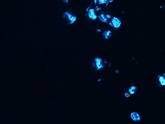

UV fluorescence microscopic image (Nikon) of B16 melanoma after uptake of AuSPION . The image is shifted from green to blue due to the uptake of gold nanoparticles (x 60)

In the scattering image, the gold coated maghemite nanoparticles surrounded by melanoma can be seen as bright blue areas in UV light.